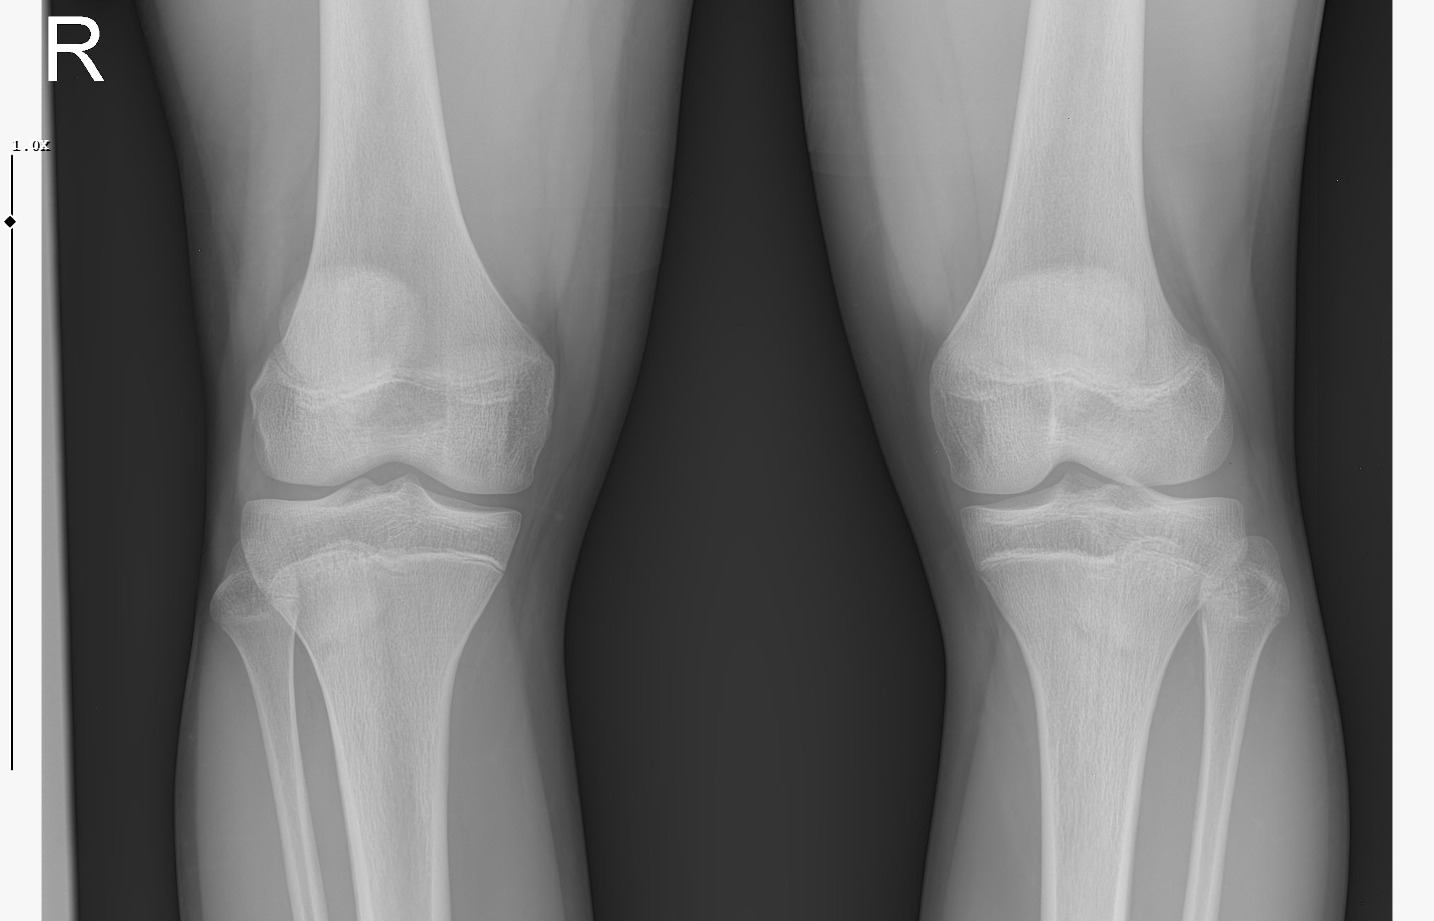

doktor bi sik bilmiyodur büyük ihtimalle plakları buraya at biz bakak

bide bir sekilde hgh temin et babandan kısasın uzama olasılığın çok daha fazla gh ile,şuan ona paran yoksa da biriktirmeye başla aromasin kullan

IMG 5959

röntgeni atar mısın?

böyle ne diyorsun yaşım genc bu arada

Attachments

• WhatsApp Image 2026-01-07 at 00.31.08 (4).jpeg

WhatsApp Image 2026-01-07 at 00.31.08 (4).jpeg

161.8 KB · Views: 0

• WhatsApp Image 2026-01-07 at 00.31.08 (3).jpeg

WhatsApp Image 2026-01-07 at 00.31.08 (3).jpeg

104.8 KB · Views: 0

• WhatsApp Image 2026-01-07 at 00.31.08 (1).jpeg

WhatsApp Image 2026-01-07 at 00.31.08 (1).jpeg

140.5 KB · Views: 0

• WhatsApp Image 2026-01-07 at 00.31.08.jpeg

WhatsApp Image 2026-01-07 at 00.31.08.jpeg

138.6 KB · Views: 0

kapanmaya baslamıs ama cok yakın degil

kemik yaşın 15 gibi 15'e çok yakın

anne baba boyun ve yaşını bilmiyorum sadece bu bilgilerle 171-175 arası diye tahmin ediyorum röntgen ile.

normalde anne babana göre 171-176 olman gerek zaten. kemik yaşın ve şuanki boyun ile yapılacak tahmin anne baban ile yapılabilecek tahminle nerdeyse birebir aynı yani büyük ihtimal o civarlar olursun bence